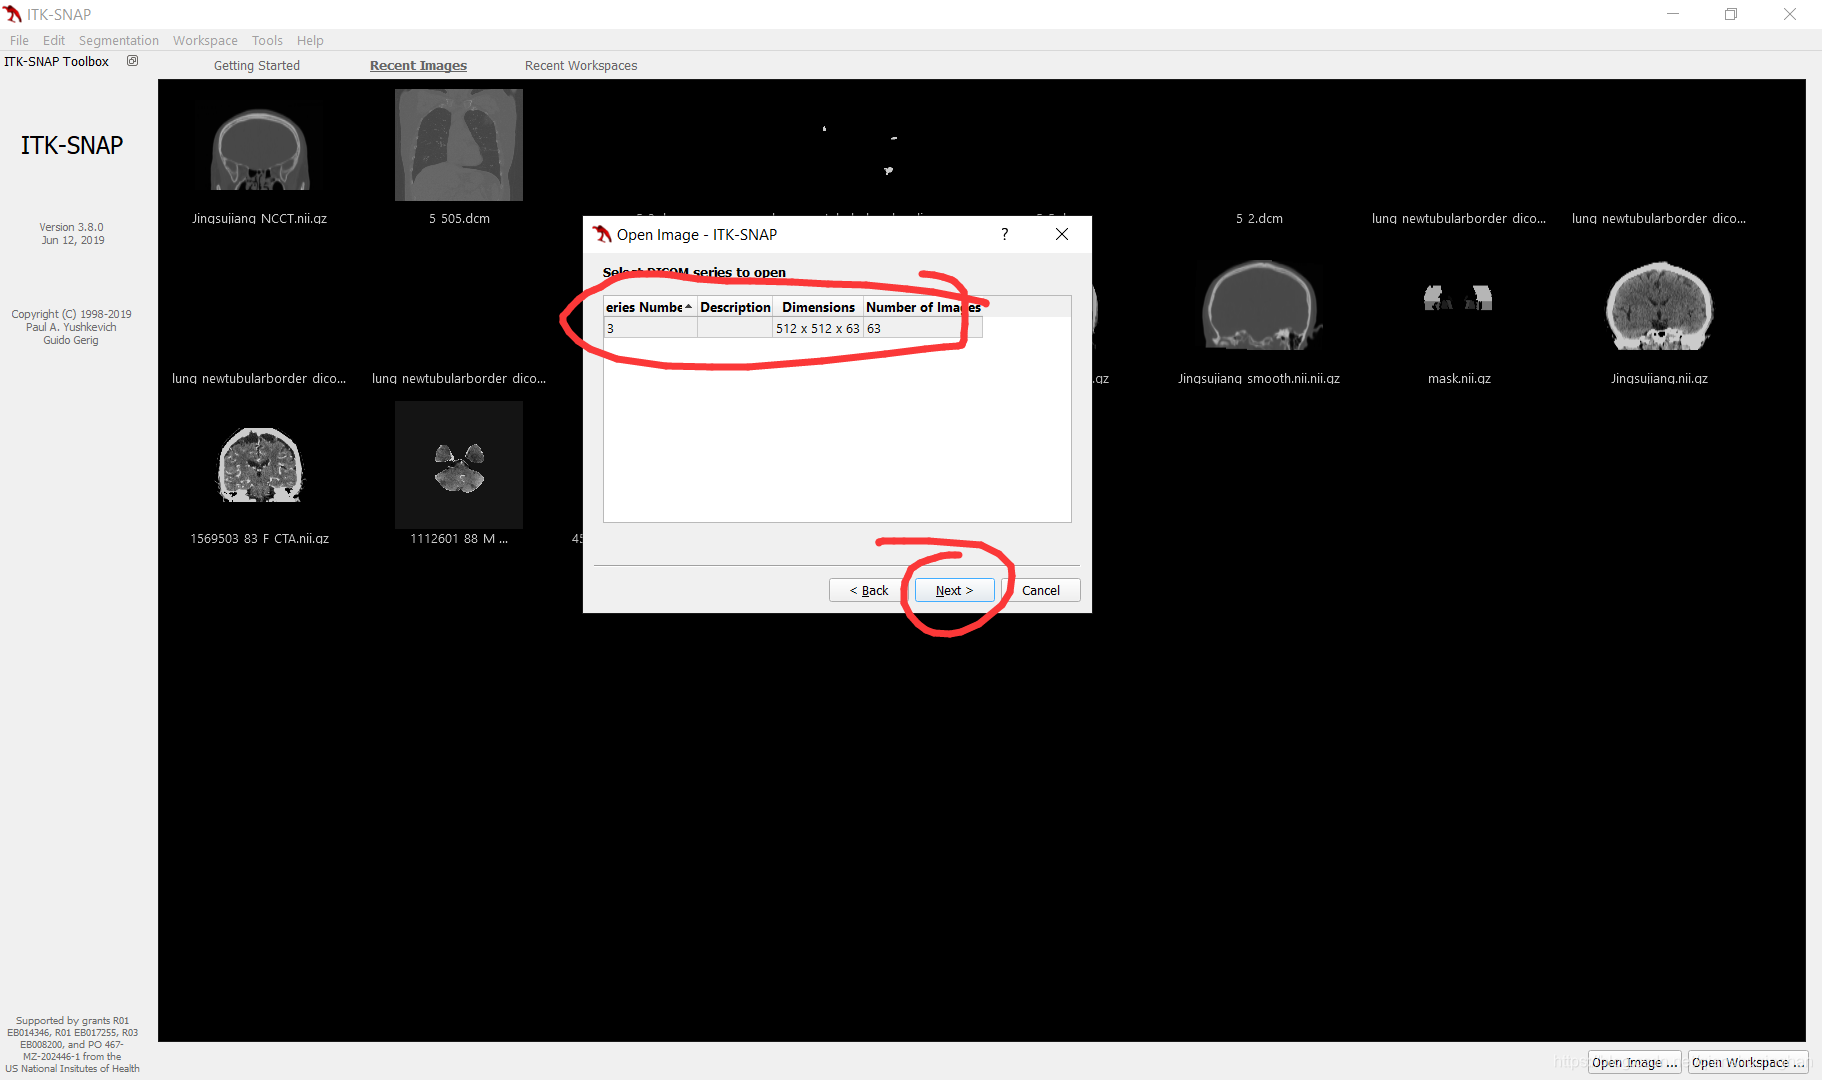

导入图像

可采用拖拽、或者File->Open Main Image两种方式导入图像(支持dicom,nifity等格式文件)

如文件夹下含多个图像序列,此处会显示多个序列列表,选中待勾画序列,电极下一步即可导入,最后点击finish